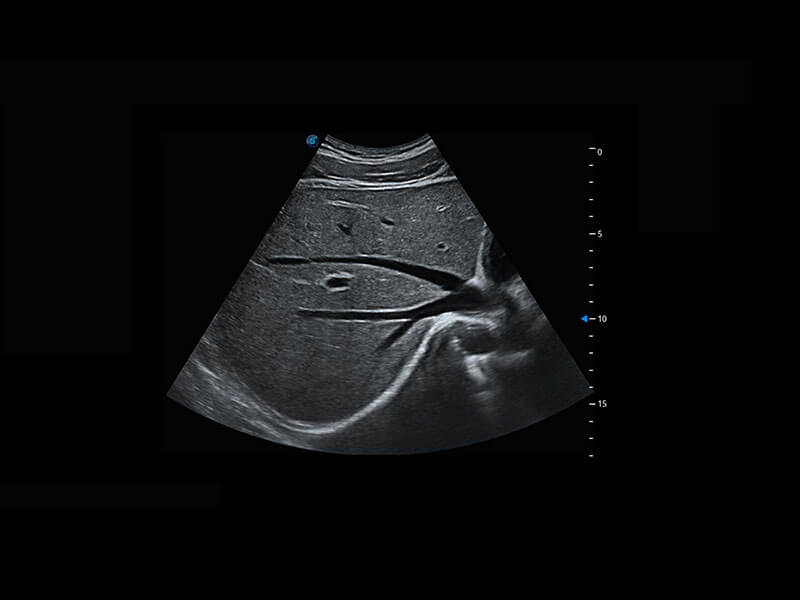

P60搭载宽频带线阵探头、宽景成像、弹性成像技术,为您提供乳腺应用方案。P60支持高频相控阵探头、线阵探头、腹部高频探头、腹部微凸探头等,丰富的探头群搭载敏感的彩色血流成像,适用于新生儿多种脏器检测要求,满足新生儿筛查需求。

新生儿肝血管癌

新生儿脊髓圆锥

新生儿心脏